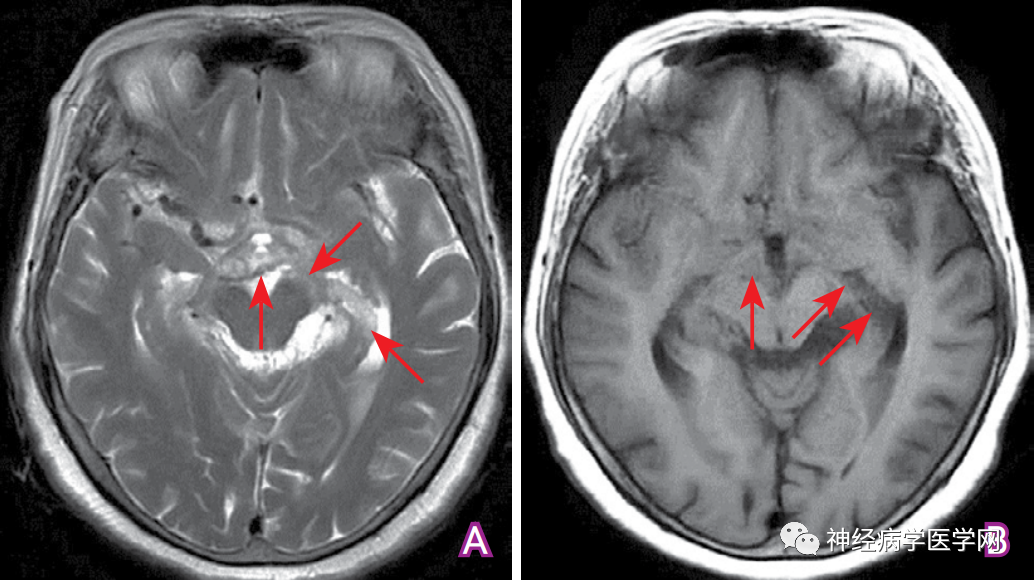

图7 蛛网膜下腔出血的MRI影像表现 A:T2WI序列显示部分脑池、脑沟信号降低(箭头所示);B:T1WI序列显示相应脑池、脑沟信号较侧脑室内脑脊液信号高(箭头所示);C:T2 FLAIR序列显示多处脑池、脑沟呈高信号改变(箭头所示);D:SWI序列显示脑沟、脑池呈弥漫分布低信号改变 (箭头所示)。